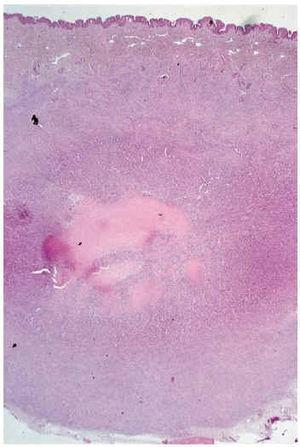

El estudio histopatológico mostró a nivel de dermis y tejido celular subcutáneo una lesión tumoral relativamente circunscrita, aunque de límites imprecisos, en la que se apreciaba una arquitectura zonal. En la periferia había una proliferación de células fusiformes, dispuestas en fascículos entrelazados o arremolinados, de patrón leiomiomatoso, separados por finas bandas de colágeno; en la zona intermedia, células de pequeño tamaño, separadas por espacios vasculares irregulares, de patrón hemangiopericitoide; finalmente existía una zona central de hialinización (fig. 2). No existía atipia celular, siendo infrecuentes las mitosis. En la periferia, la tumoración mostraba tendencia a infiltrar el tejido adiposo, así como los fascículos musculares presentes en el borde profundo. Asimismo se apreciaban imágenes de crecimiento intravascular.

Fig. 2.--Lesión nodular en dermis y tejido celular subcutáneo con tres áreas histológicamente distintas: zona periférica de patrón leiomiomatoso, zona intermedia de patrón hemangiopericitoide y zona central hialinizada.